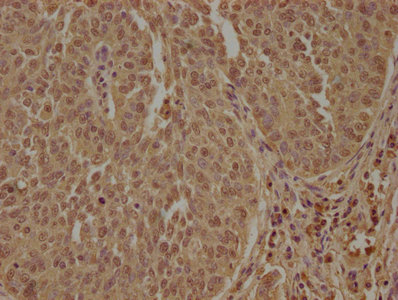

• IHC image of CSB-PA851965OA01HU diluted at 1:100 and staining in paraffin-embedded human cervical cancer performed on a Leica BondTM system. After dewaxing and hydration, antigen retrieval was mediated by high pressure in a citrate buffer (pH 6.0). Section was blocked with 10% normal goat serum 30min at RT. Then primary antibody (1% BSA) was incubated at 4°C overnight. The primary is detected by a biotinylated secondary antibody and visualized using an HRP conjugated SP system.